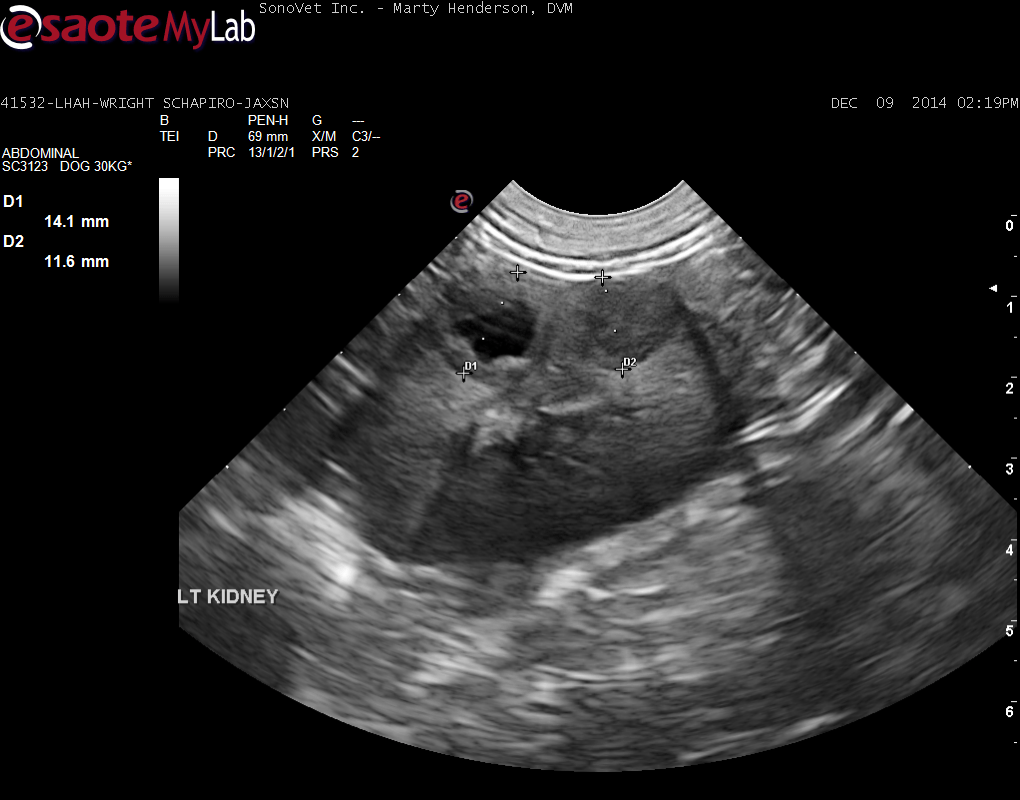

A 7-year-old MN Shepherd Mix was presented for evaluation of tenesmus with no other obvious signs. On rectal palpation a mass on the ventral aspect of the lumbar spine that starts approximately 0.5 cm into the pelvic canal and extends cranial for about an inch